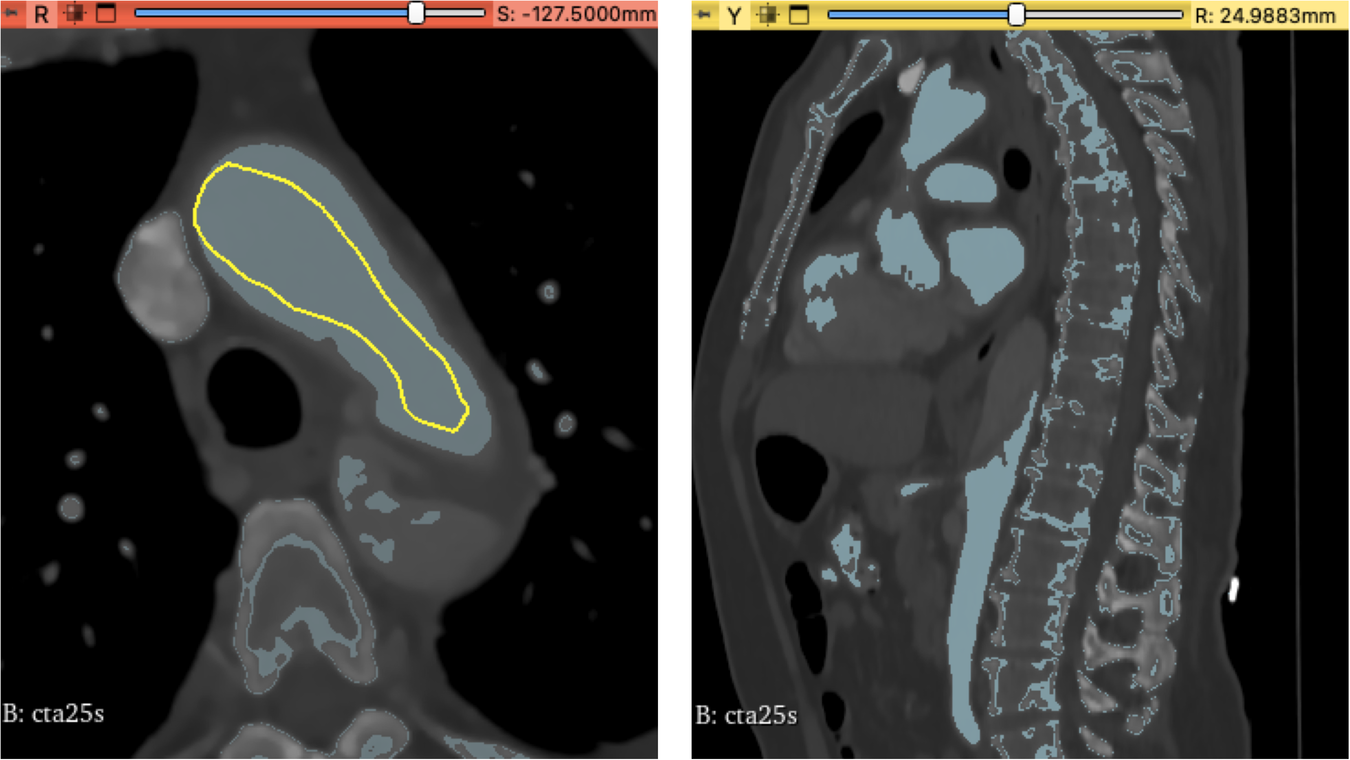

Fig. 2

Local thresholding has been applied to the true lumen within the aortic arch of cta25s as seen here in the axial and sagittal plane. A light blue tone indicates regions to be part of the segmentation. As seen not all regions like bone structures or cardiac chambers have been mapped correctly therefore this method needed a lot of manual post-processing.